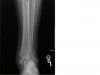

Here's what happened to a buddy last year when he bailed and landed on his foot (came up short on a double). I still remember seeing him fall "out of the sky". :shocked: :crash:

39539_1415671120005_1479410673_30853941_6254917_n.jpg

His boots weren't the greatest and allowed a lot of side bending, he now has new/better boots. :smirk:

View attachment 2741